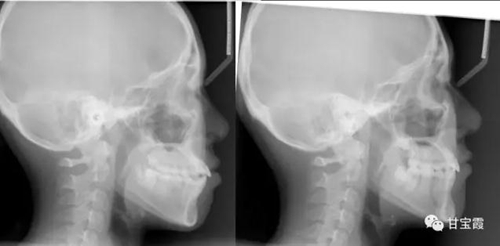

下面的矯正前后的對比照片看出側(cè)貌得到了改善

6.jpg